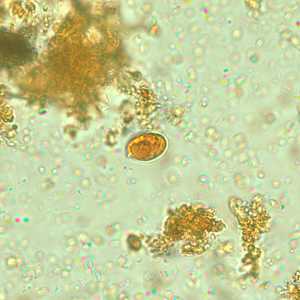

E. polecki cyst in a concentrated wet mount, stained with iodine.

Figure A: Cyst of E. polecki in a wet mount, stained with iodine. Notice the numerous chromatoid bodies (arrows).